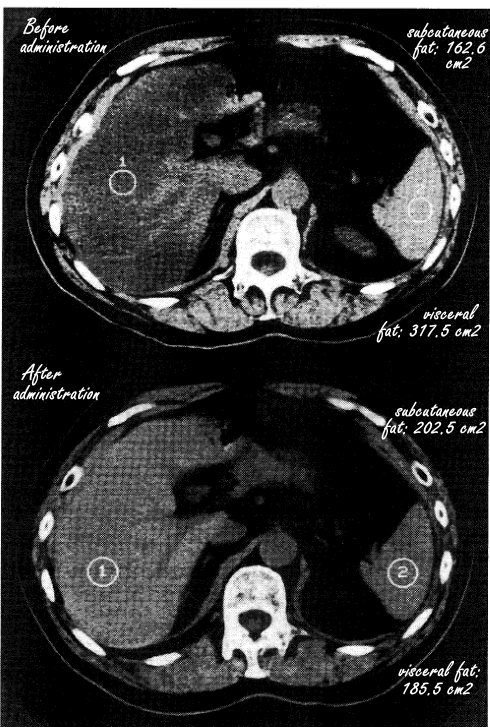

During the supplementation period, according to scans, the amount of fat in the liver and the amount of visceral fat decreased significantly. On the scans below the table you see scans of a representative subject.

The conclusion of the Japanese is obvious. "Pantethine improved fatty liver with hypertriglyceridemia and reduced visceral fat," they write.

Opposite the decrease of the abdominal fat may be an increase in the subcutaneous fat. (Yep, the latter effect was not statistically significant, but that might have been different in a study with more subjects.) It would be interesting to look at the effect of pantethine supplementation in people who, due to a slimming diet or a physical exercise program, are ingesting fewer kilocalories than they burn.